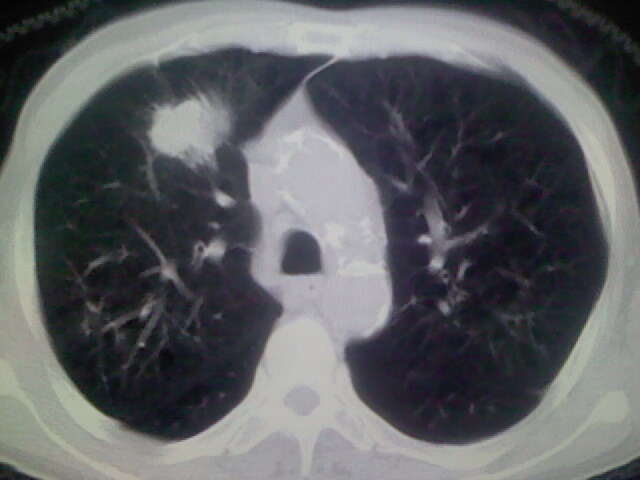

男,70y,胃占位,重度贫血,黑便3月余,伴恶心,纳差,乏力

胃癌,并肝,右肺,右径部,纵隔淋巴结转移

胃癌,并肝,右肺,右颈部,纵隔淋巴结转移

1)考虑右肺上叶周围型肺癌并纵隔及右颈部淋巴结转移,肝脏多发性转移。2)肺气肿。3)冠状动脉及主动脉钙化。

资料不清晰啊,肺内病灶内可见多发钙化影,结核不能除外.肝内符合转移瘤表现.既然楼主提供胃内占位,那原发灶还是考虑来源于胃腔.